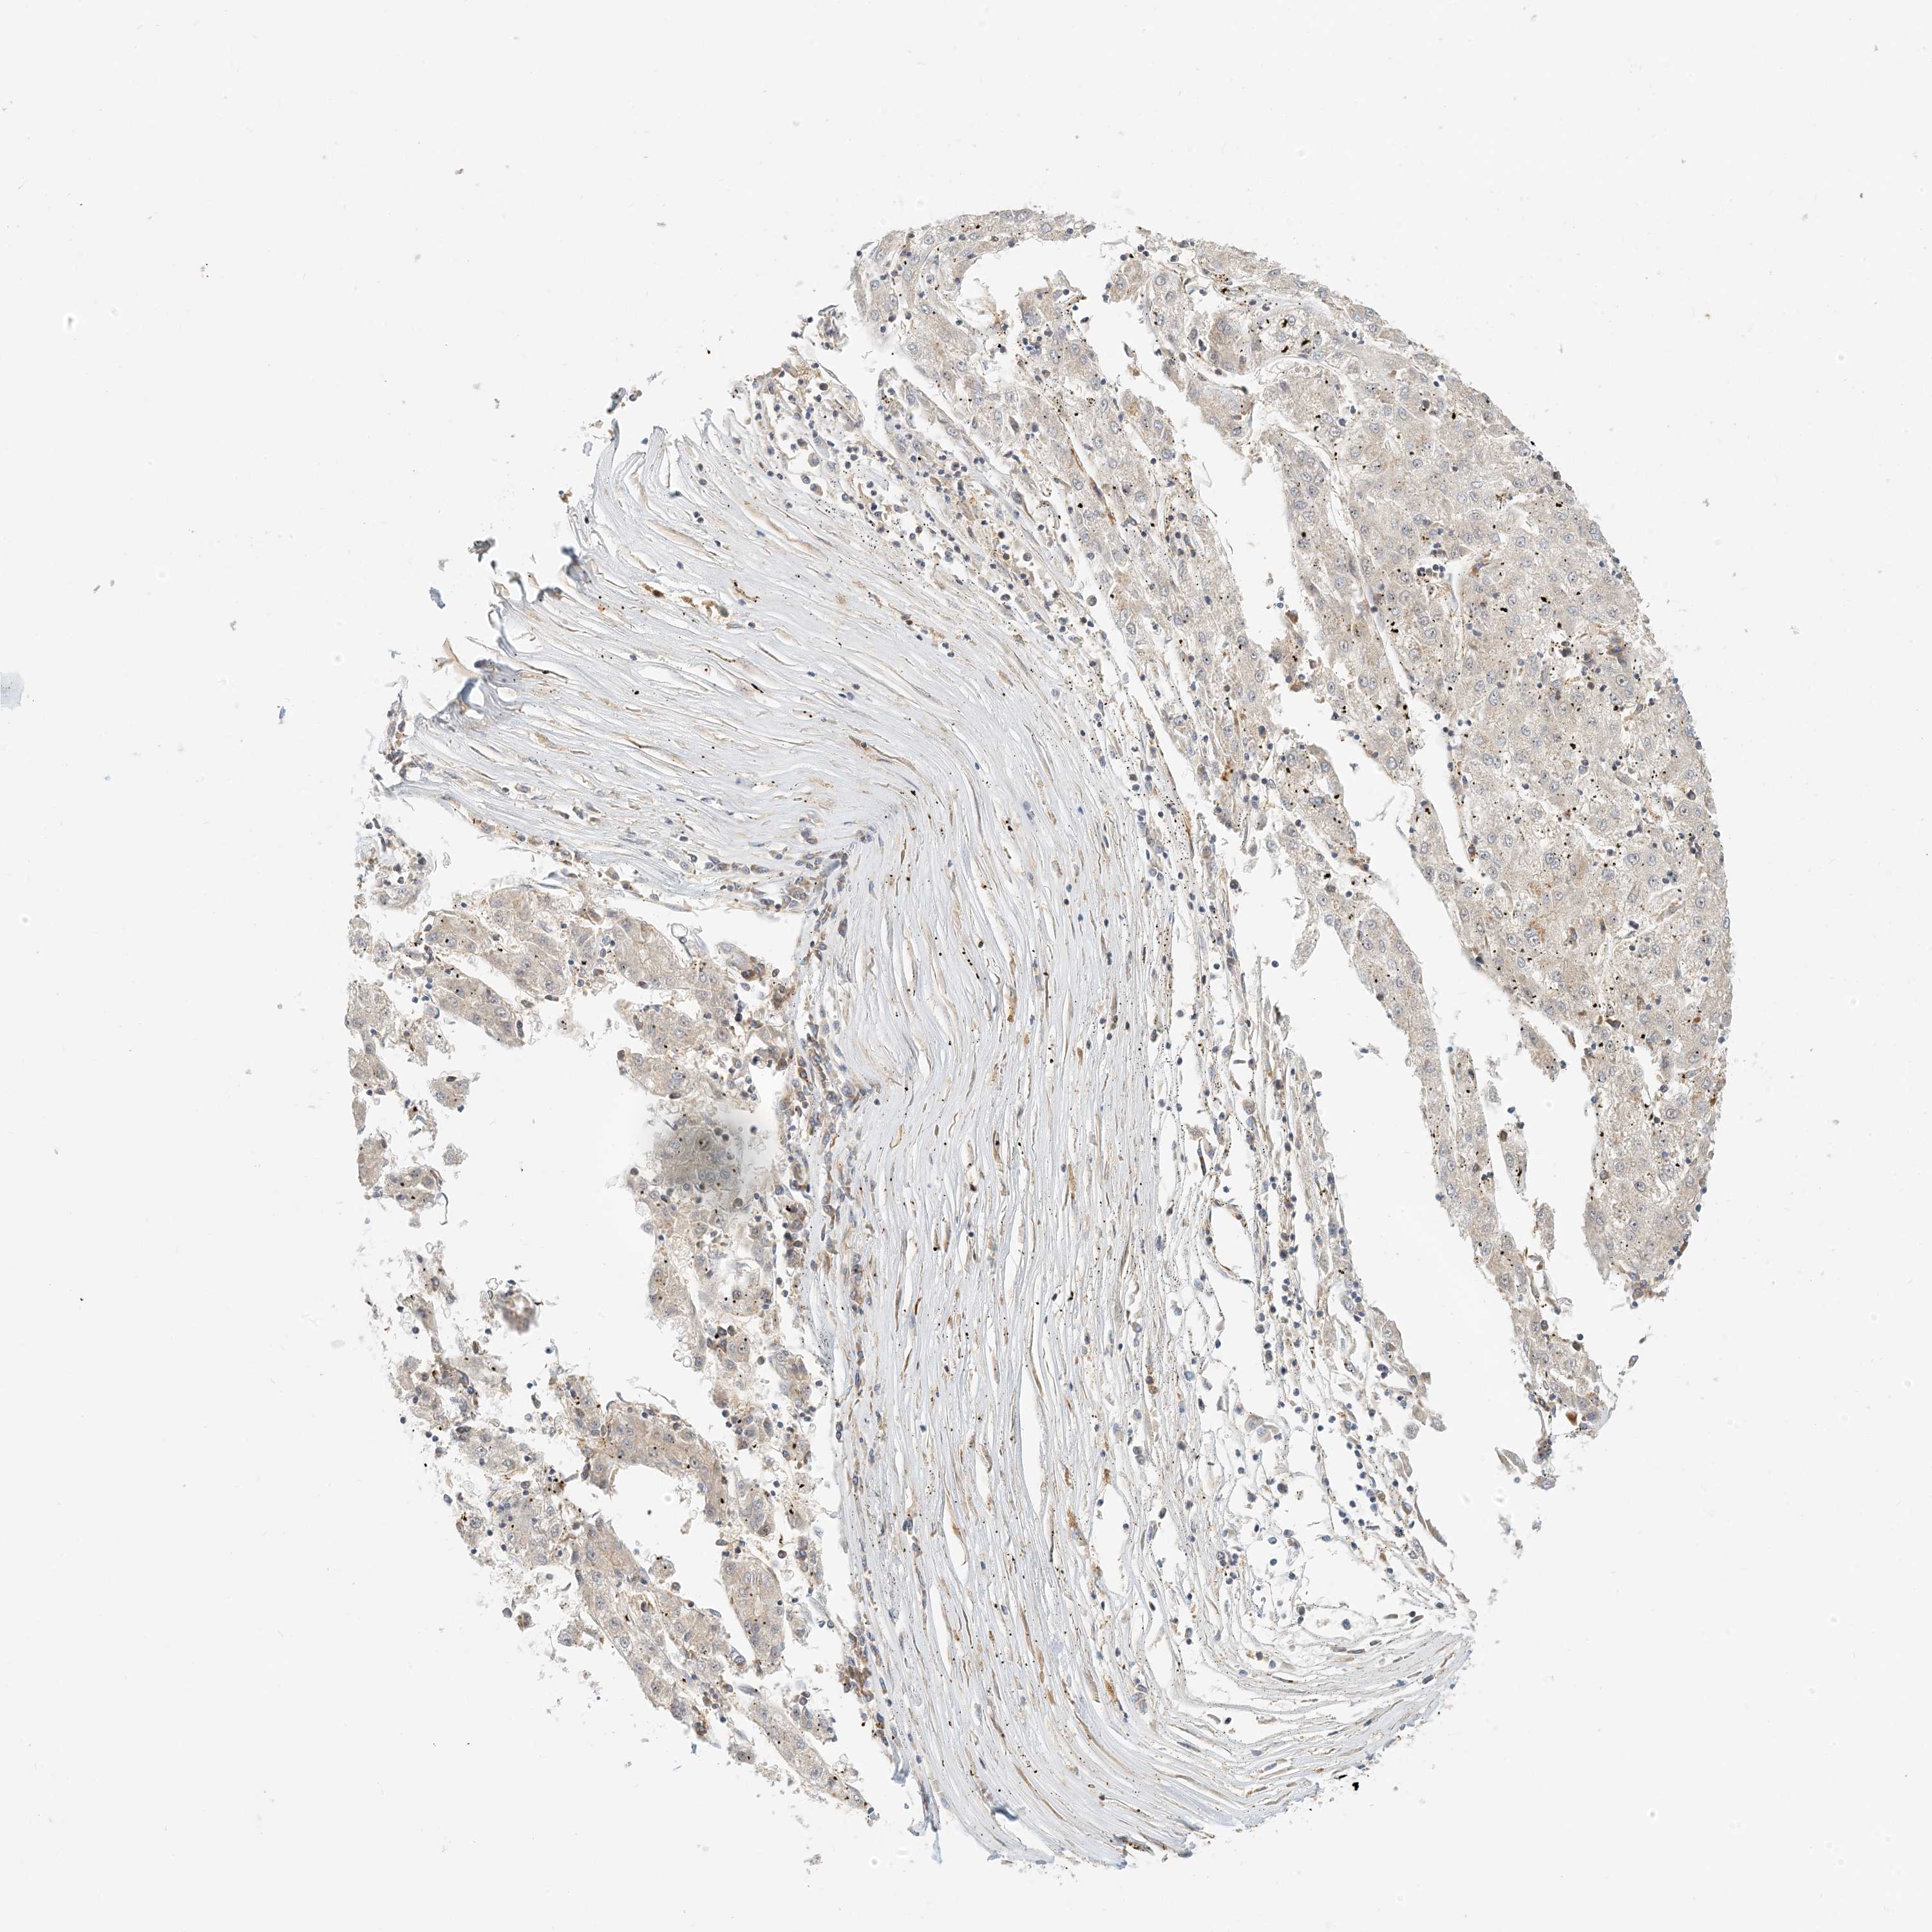

LIVER CANCER - Protein expressioni

A mouse-over function shows sample information and annotation data. Click on an image to view it in a full screen mode. Samples can be filtered based on level of antibody staining by selecting one or several of the following categories: high, medium, low and not detected. The assay and annotation is described here.

Note that samples used for immunohistochemistry by the Human Protein Atlas do not correspond to samples in the TCGA dataset.

Antibody stainingi

Antibody staining in the annotated cell types in the current human tissue is reported as not detected, low, medium, or high, based on conventional immunohistochemistry profiling in selected tissues. This score is based on the combination of the staining intensity and fraction of stained cells.

Each image is clickable and will lead to virtual microscopy that enables deeper exploration of all samples and also displays staining intensity scores, fraction scores and subcellular localization as well as patient and tissue information for each sample.

Antibody HPA035241

Staining

High

Medium

Low

Not detected

Intensity

Strong

Moderate

Weak

Negative

Quantity

>75%

75%-25%

<25%

None

Location

Nuclear

Cytoplasmic/membranous

Cytoplasmic/membranous,nuclear

Cholangiocarcinoma

Carcinoma, Hepatocellular, NOS